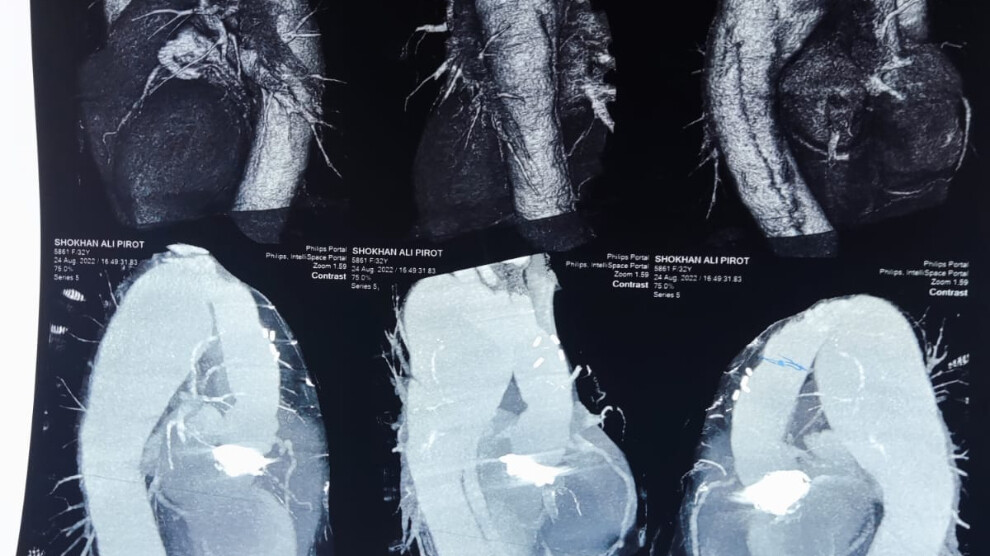

بەڕێوەبەرایەتی گشتی تەندروستی سلێمانی بڵاویکردەوە، بۆ یەکەمجار لە نەخۆشخانەی پسپۆڕییەكانی دڵ نەشتەرگەرییەكی دەگمەن لەسەر ئاستی عێراق و هەرێمی کوردستان بە سەركەوتوویی ئەنجامدراوە و نەخۆشێک لە مردن ڕزگاری بووە.

لە بڵاوکراوەکە ئاماژە بەوەکراوە، لە نەخۆشخانەی پسپۆڕییەكانی دڵ لە شاری سلێمانی، بەهەوڵ و ماندبوونی پزیشكانی پسپۆڕی نەشتەرگەری دڵ و ستافی تەندروستی ئەو نەخۆشخانەیە نەشتەرگەری گەورەی گۆڕینی شاخونێبەر بۆ هاووڵاتییەک ئەنجامدراوە و لە مردن ڕزگاری بووە.

پزیشک شکار رەئوف لێپرسراوی بەشی نەشتەرگەریی دڵ لە نەخۆشخانەی پسپۆڕییەکانی دڵ لە شاری سلێمانی ئاشکرایکرد، توانراوە بە ئەنجامدانی نەشتەرگەرییەکی گەورە بۆ گەنجێک، کە بریتیبوو لە گۆڕینی شاخوێنبەری سنگ کە تووشی هەوکردنی بەشی خوارەوەی شاخوێنبەر ببوو.